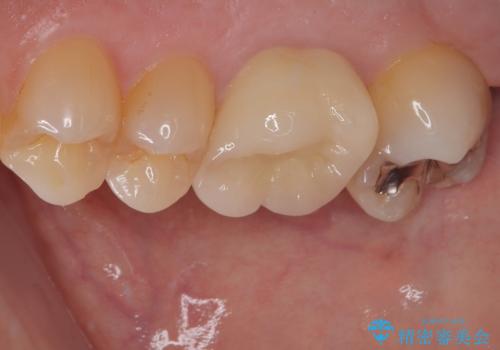

- 以前他院で治療した銀歯が外れてしまったとのことで来院された患者様です。

精査の結果、歯の神経は問題ないですが、欠損している範囲が大きいため部分的な詰め物では脱離や破折のリスクが高いため、オールセラミッククラウンによる補綴治療を行っていくこととしました。

適合の良い治療は再度虫歯になるリスクが低いです。